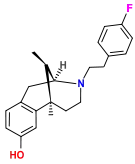

Benzomorphans

- 5,9 alpha-diethyl-2-hydroxybenzomorphan (5,9-DEHB)

- 8-Carboxamidocyclazocine (8-CAC)

- Alazocine

- Anazocine

- Bremazocine

- Butinazocine

- Carbazocine

- Cogazocine

- Cyclazocine

- Dezocine

- Eptazocine

- Etazocine

- Ethylketazocine

- Fedotozine

- Fluorophen

- Gemazocine

- Ibazocine

- Ketazocine

- Metazocine

- Moxazocine

- Pentazocine

- Phenazocine

- Quadazocine

- SKF-10047

Structures

| Benzomorphans | ||||

|---|---|---|---|---|

5,9 alpha-diethyl-2-hydroxybenzomorphan 5,9 alpha-diethyl-2-hydroxybenzomorphan (5,9-DEHB) |

8-Carboxamidocyclazocine 8-Carboxamidocyclazocine |

Alazocine Alazocine |

Anazocine Anazocine |

Bremazocine Bremazocine |

Butinazocine Butinazocine |

Carbazocine Carbazocine |

Cogazocine Cogazocine |

Cyclazocine Cyclazocine |

Dezocine Dezocine |

Eptazocine Eptazocine |

Etazocine Etazocine |

Ethylketocyclazocine Ethylketocyclazocine |

Fedotozine Fedotozine |

Fluorophen Fluorophen |

Gemazocine Gemazocine |

Ibazocine Ibazocine |

Ketazocine Ketazocine |

Metazocine Metazocine |

Moxazocine Moxazocine |

Pentazocine Pentazocine |

Phenazocine Phenazocine |

Quadazocine Quadazocine

|

Thiazocine Thiazocine |

Tonazocine Tonazocine |

Volazocine Volazocine |

Zenazocine Zenazocine |